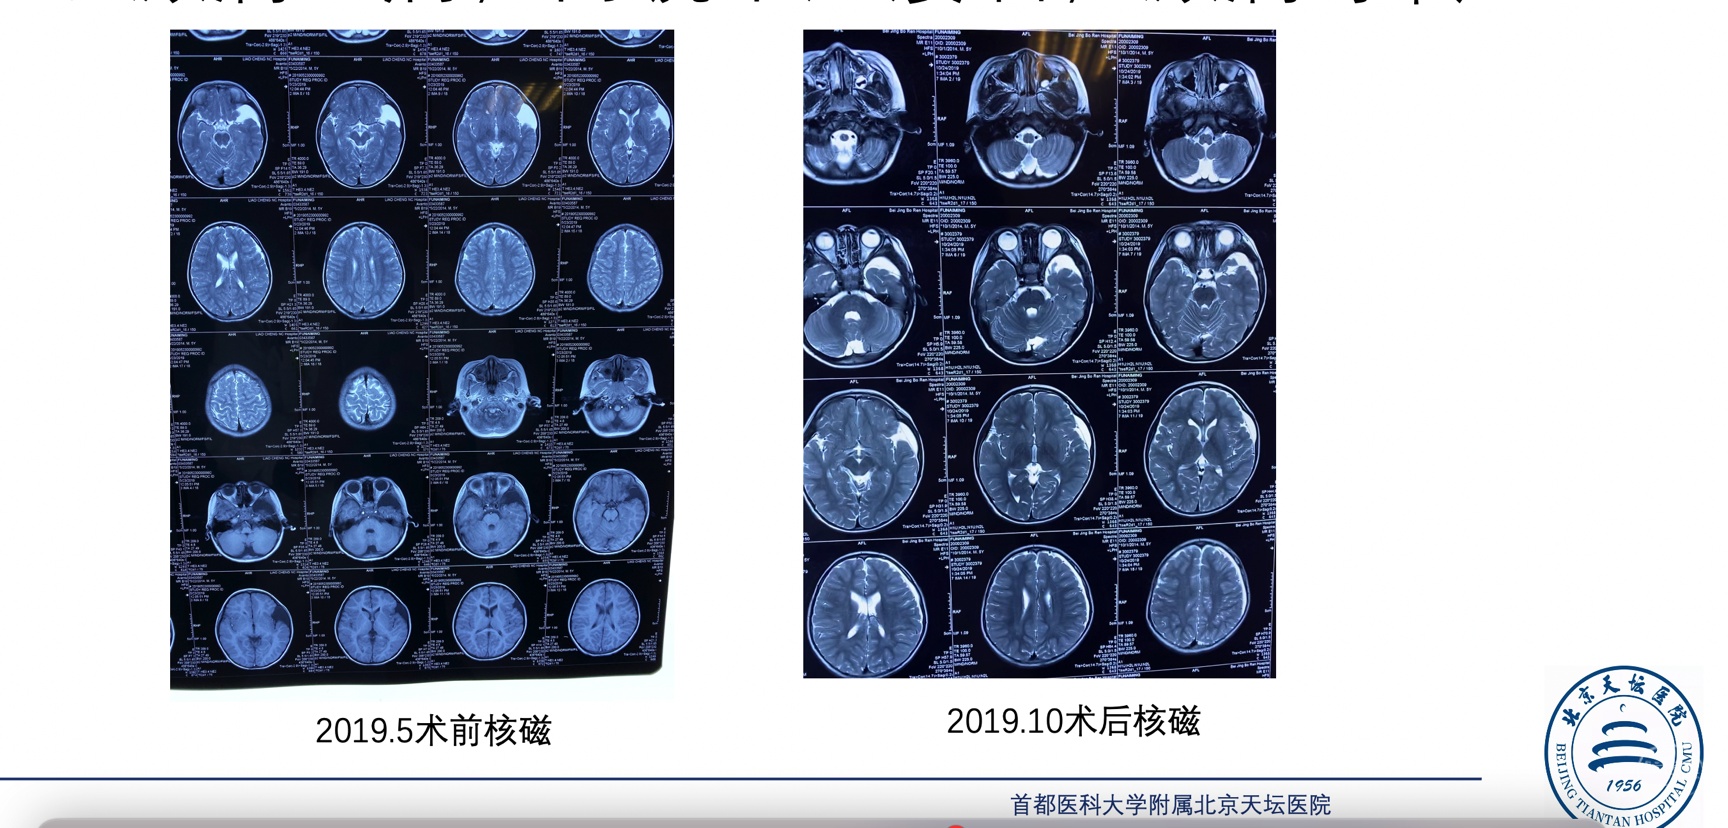

病例二 患儿5岁,左侧外侧裂蛛网膜囊肿,以癫痫起病,内镜下造瘘后,癫痫好转